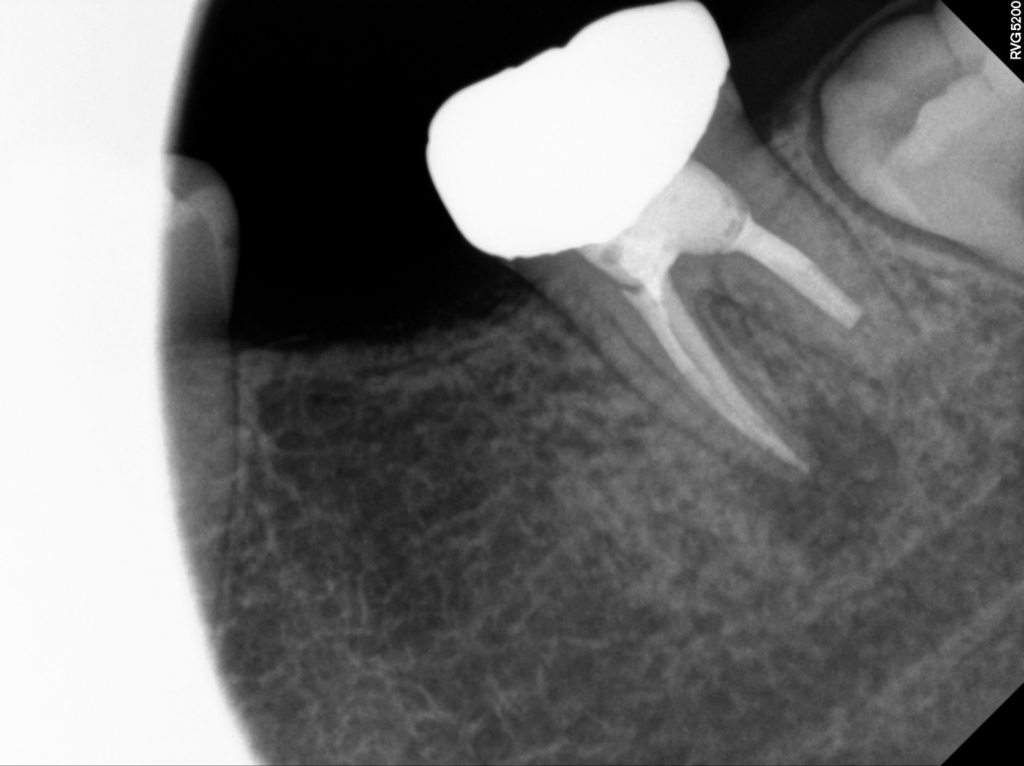

내원 당시 육안으로도 잇몸이 붓고 주변 조직이 예민한 모습이 보였으며, 정밀 촬영을 진행해보니 위 사진처럼 치근 주변에 어두운 음영의 병변이 분명하게 나타나고 있었습니다.

촬영 결과와 함께 치아 내부의 근관 상태도 면밀히 살펴본 결과, 초기 치료 과정에서 밀봉이 제대로 이루어지지 않아 세균이 다시 침투한 흔적을 확인할 수 있었고, 이에 따라 재근관치료가 필요하다고 판단하게 되었습니다.

치료 후 촬영한 사진에서는 이전과 비교해 변화된 양상을 확인할 수 있습니다.

치근 주변에 보이던 방사선 투과성 부위는 이미 뼈가 흡수된 상태라 회복 속도가 빠르지는 않지만, 그럼에도 불구하고 염증이 상당 부분 가라앉아 회복 방향이 긍정적으로 진행되고 있음을 확인했습니다.

영도치과 서울화이트S치과에서는 이번 재치료 과정에서 근관 내부의 밀봉과 차단을 꼼꼼하게 다시 시행하였고, 그 결과 치아의 흔들림과 불편감이 이전보다 줄어들어 환자분께서도 안정적인 변화를 체감하며 지속적으로 경과 관찰을 이어가고 있습니다.